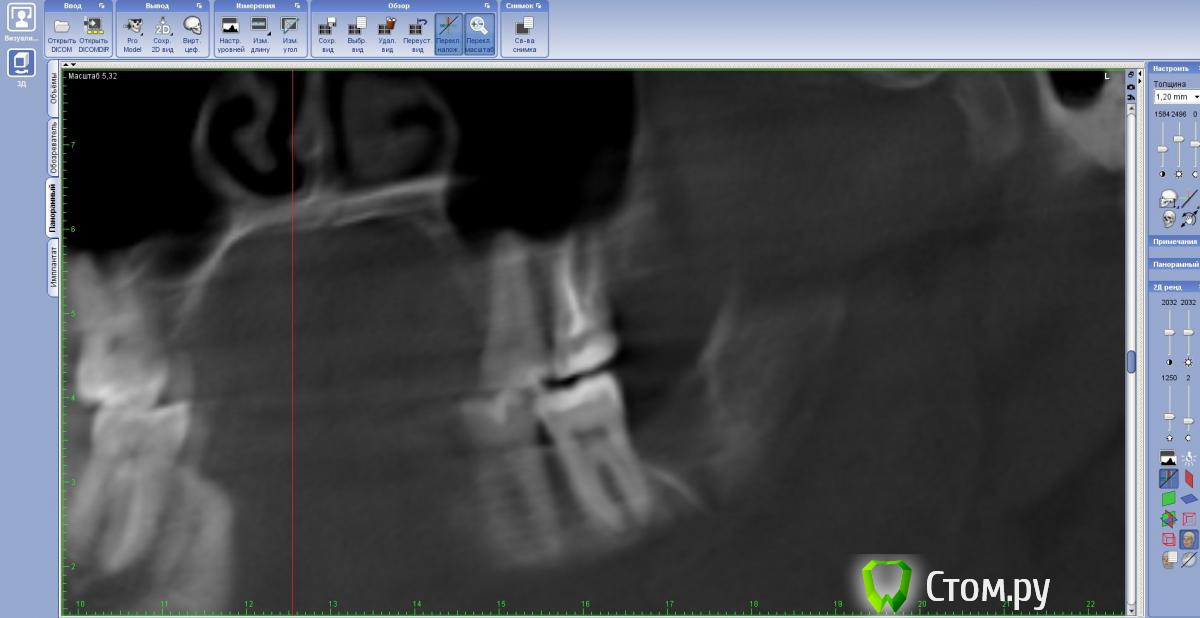

dr-krasnov Опубликовано 11 июня, 2014 Поделиться Опубликовано 11 июня, 2014 Новые снимки на засыпку, мне кажется или канал открыт? http://s019.radikal.ru/i636/1406/61/cd78fa5e3fad.jpg С 37 периапикально все ок. http://s018.radikal.ru/i515/1406/76/64d86c62cf87.jpg Ссылка на комментарий

DokDent Опубликовано 11 июня, 2014 Поделиться Опубликовано 11 июня, 2014 (изменено) Новые снимки на засыпку, мне кажется или канал открыт? С 37 периапикально все ок. Алесей Сергеевич, как в этой программе оси выставлять? Хотела сделать как в Вашем ролике (там всё суперпонятно), а здесь- как -то всё не так (скачала по ссылке №2) Изменено 11 июня, 2014 пользователем DokDent Ссылка на комментарий